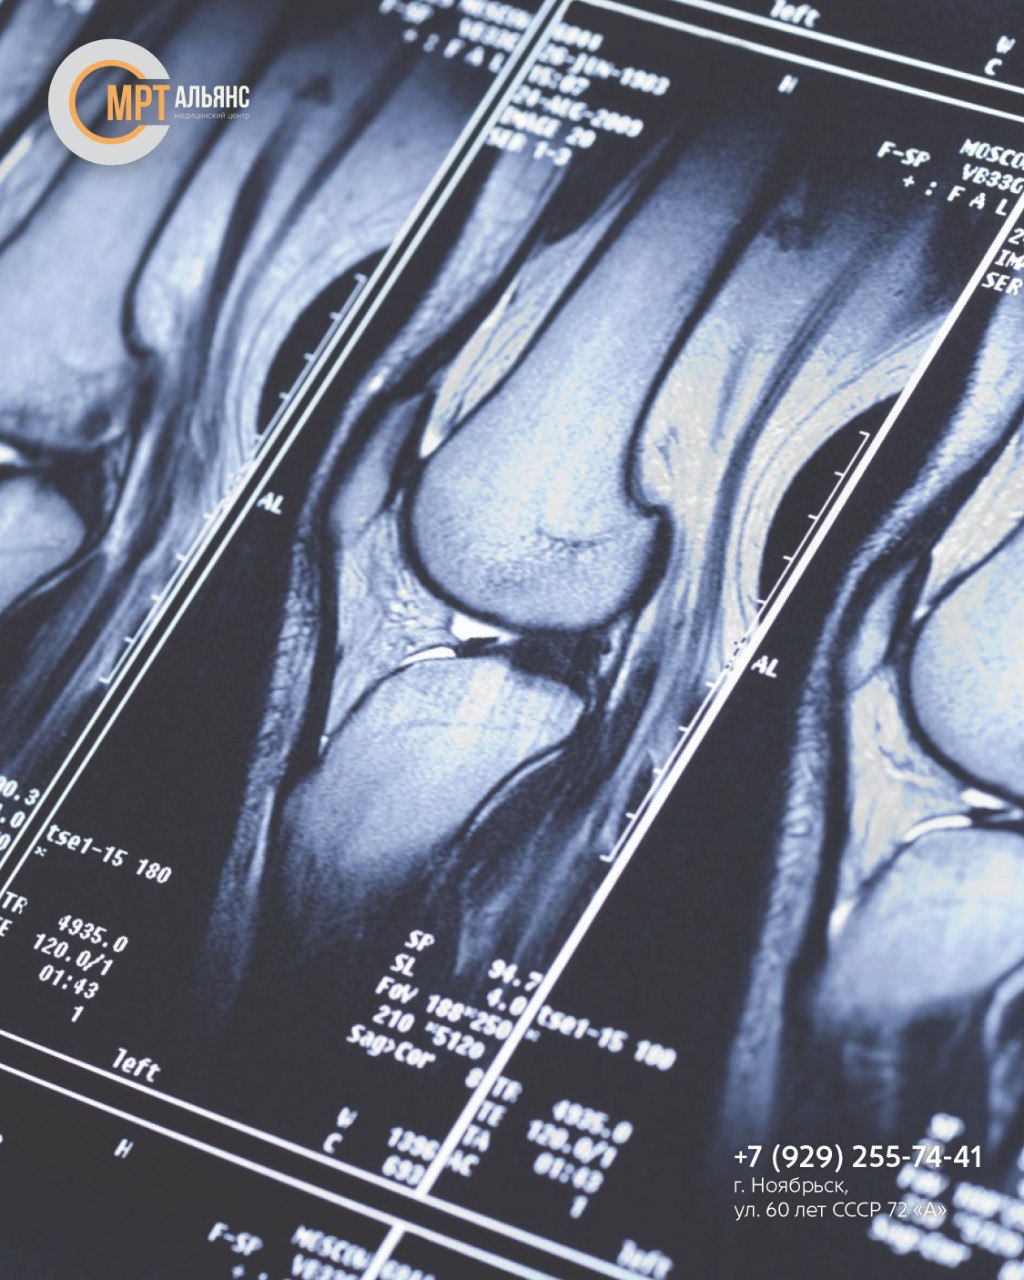

Магнитное поле проходит через исследуемую зону, отражается от анатомических структур сустава и возвращается в томограф. Датчики фиксируют интенсивность отраженных сигналов, на основе которых формируется высокоточное изображение тканей и суставных элементов

• Получение детализированного изображения исследуемой зоны